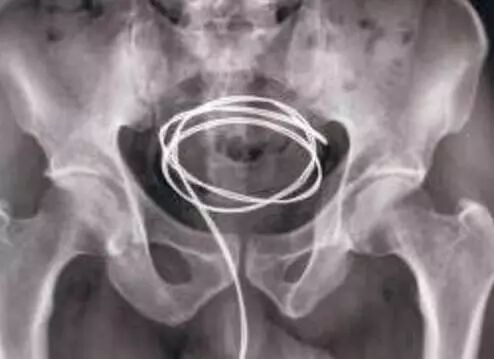

“深藏不露” ——尿道膀胱异物

曾经泌尿外科急诊来了一位痛苦万状的男性患者。询问病史得知该患者将一根橡皮管插进了膀胱已经有6小时了。最终对患者实行了急诊手术,橡皮管顺利取出。

尿道膀胱异物,顾名思义,就是尿道和膀胱里的异物,大部分是人为将异物塞进尿道或膀胱膀胱内常见异物有温度计、铁丝、铁钉、发卡、玻璃棒、铅笔、节育器(环)等。

膀胱异物的治疗方法主要有经尿道膀胱镜下异物取出和膀胱切开异物取出